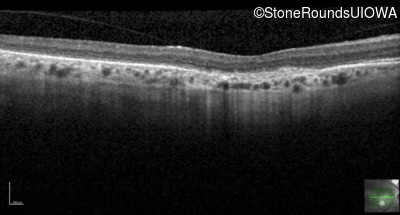

Optical Coherence Tomography - Right - 20/125 -2

Exemplar / OCT Stack